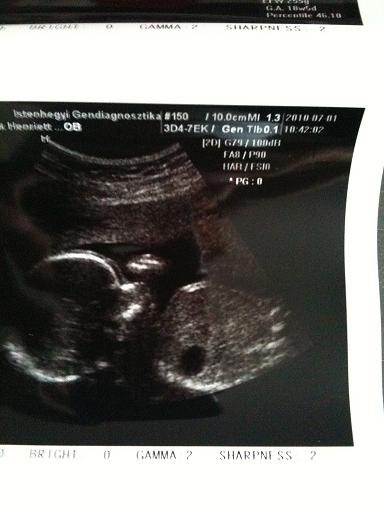

Henne ugyhogy ne felejtsd el a pocisképet!!!